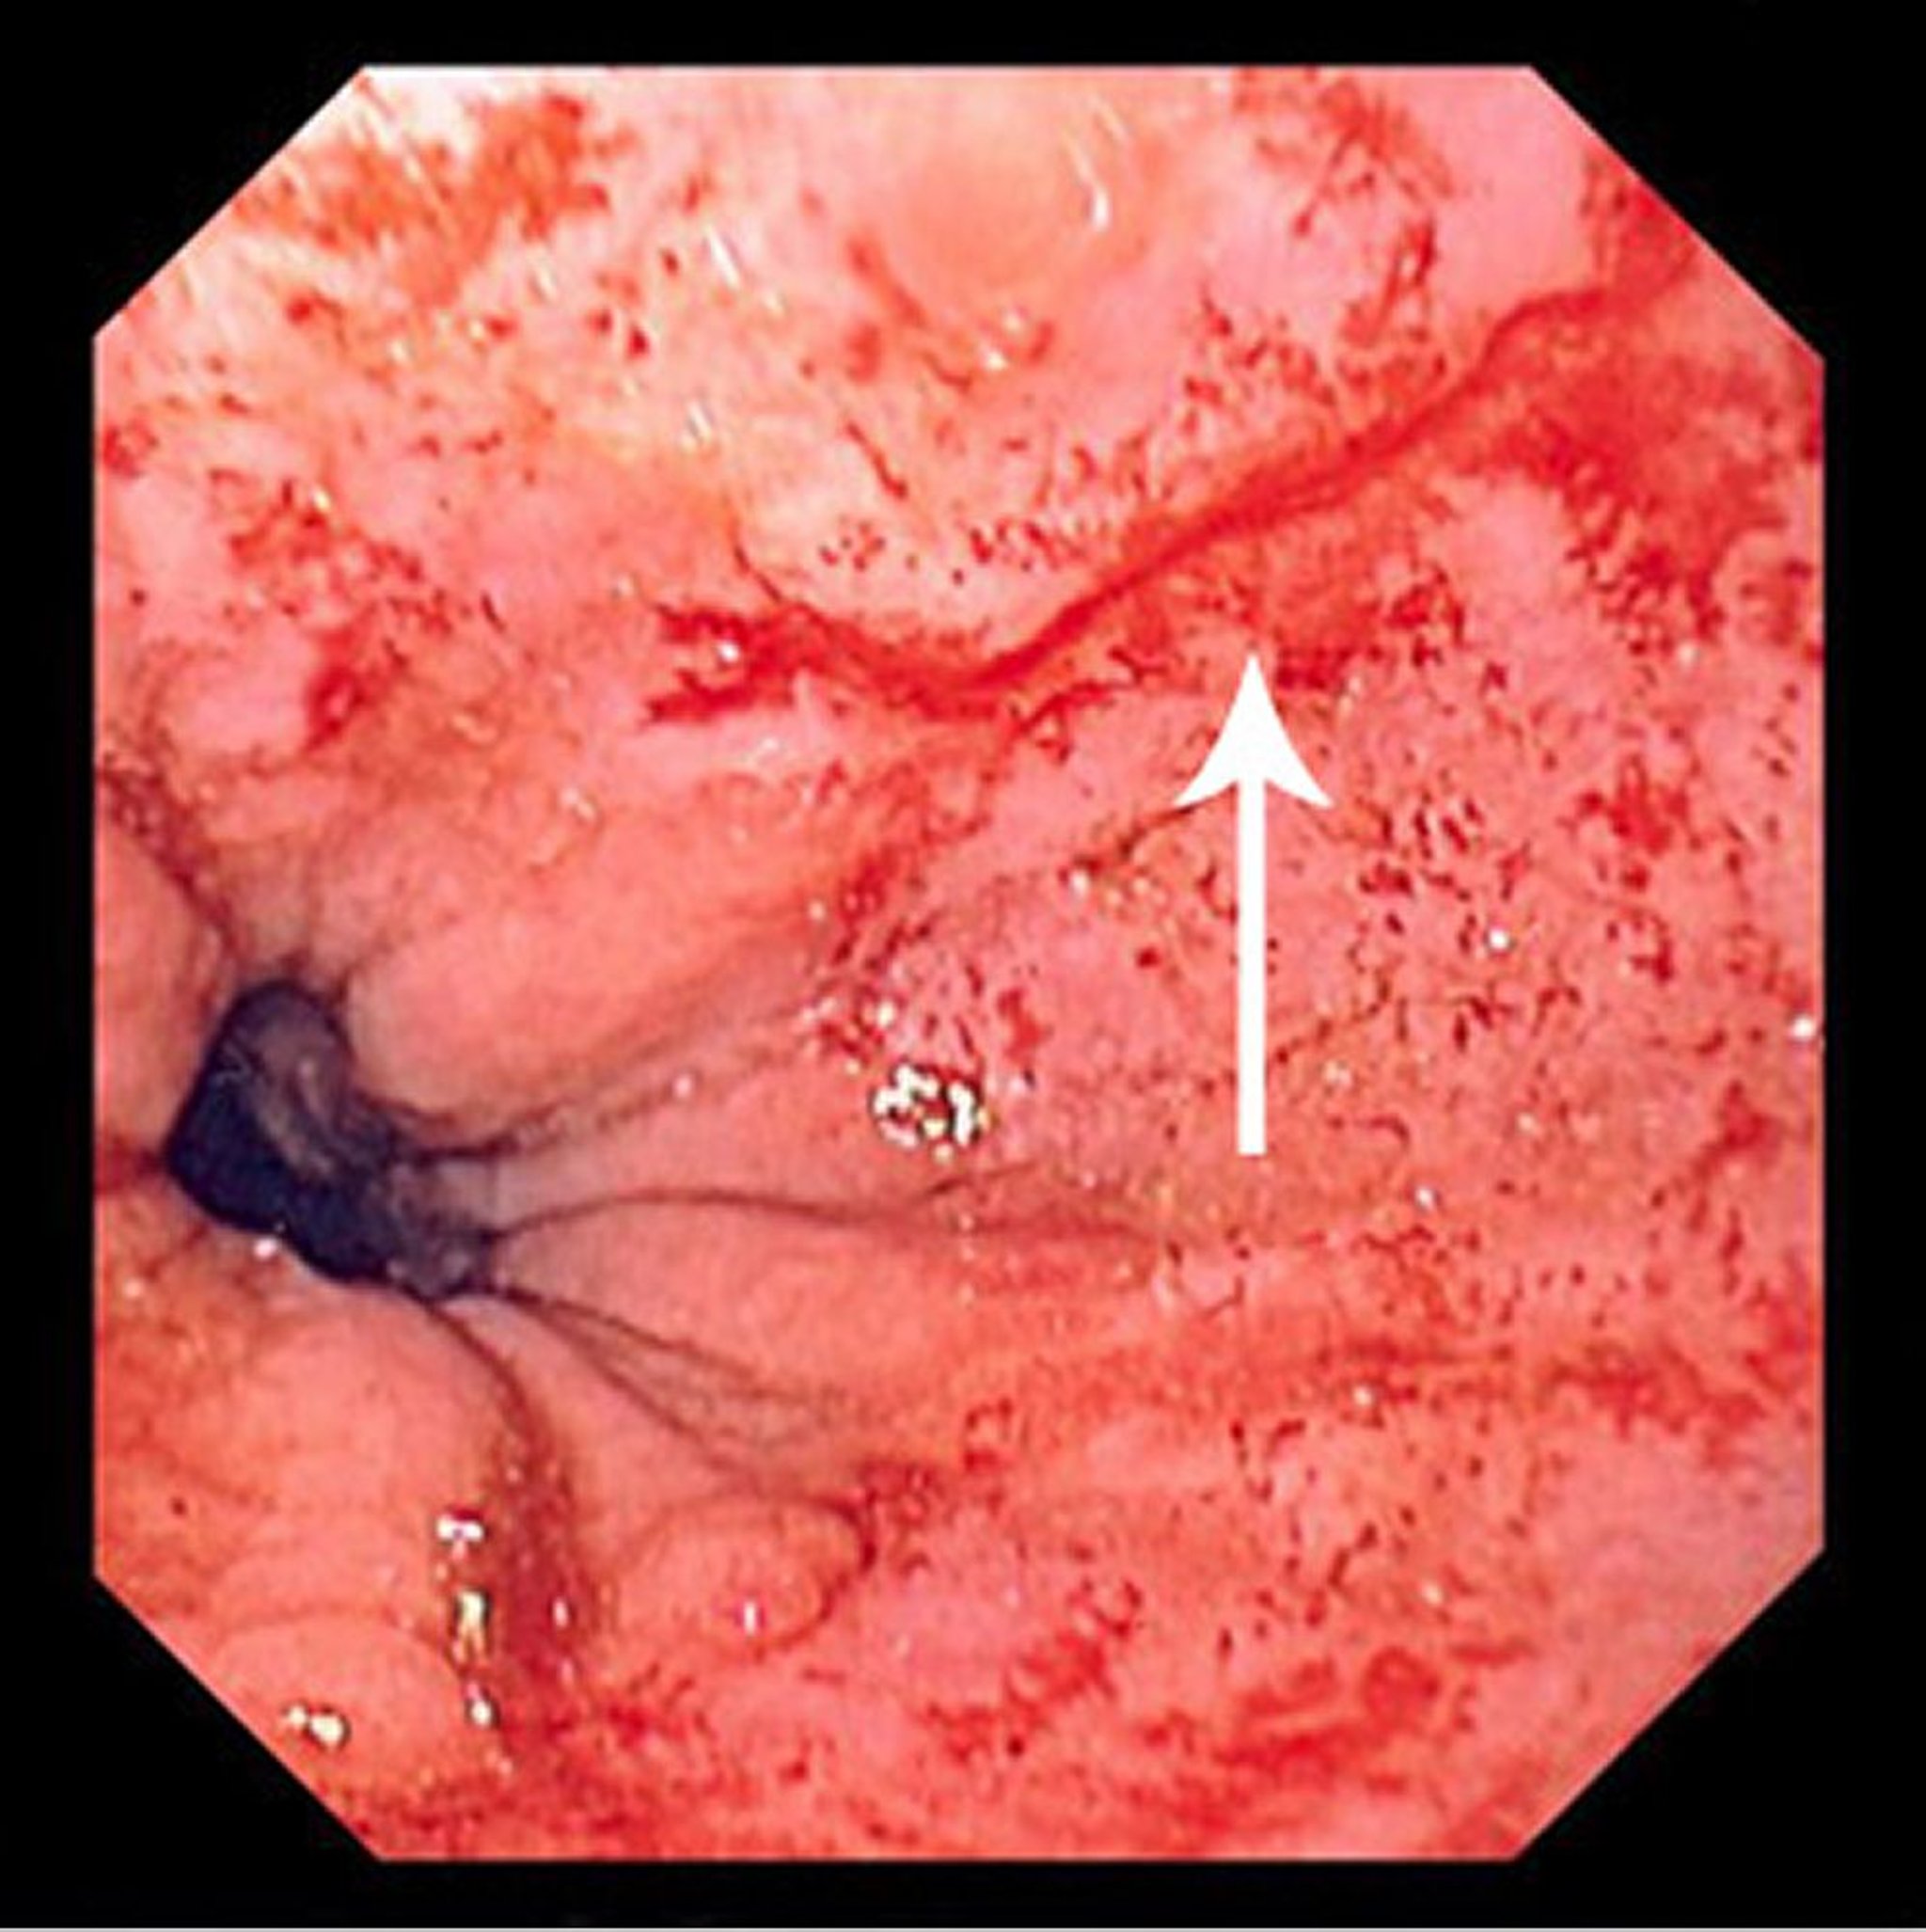

Lesão de Mallory-Weiss

Essa imagem mostra ruptura fina linear (seta) começando um pouco acima da junção escamocolunar e se estendendo em direção proximal.

Image provided by David M. Martin, MD.